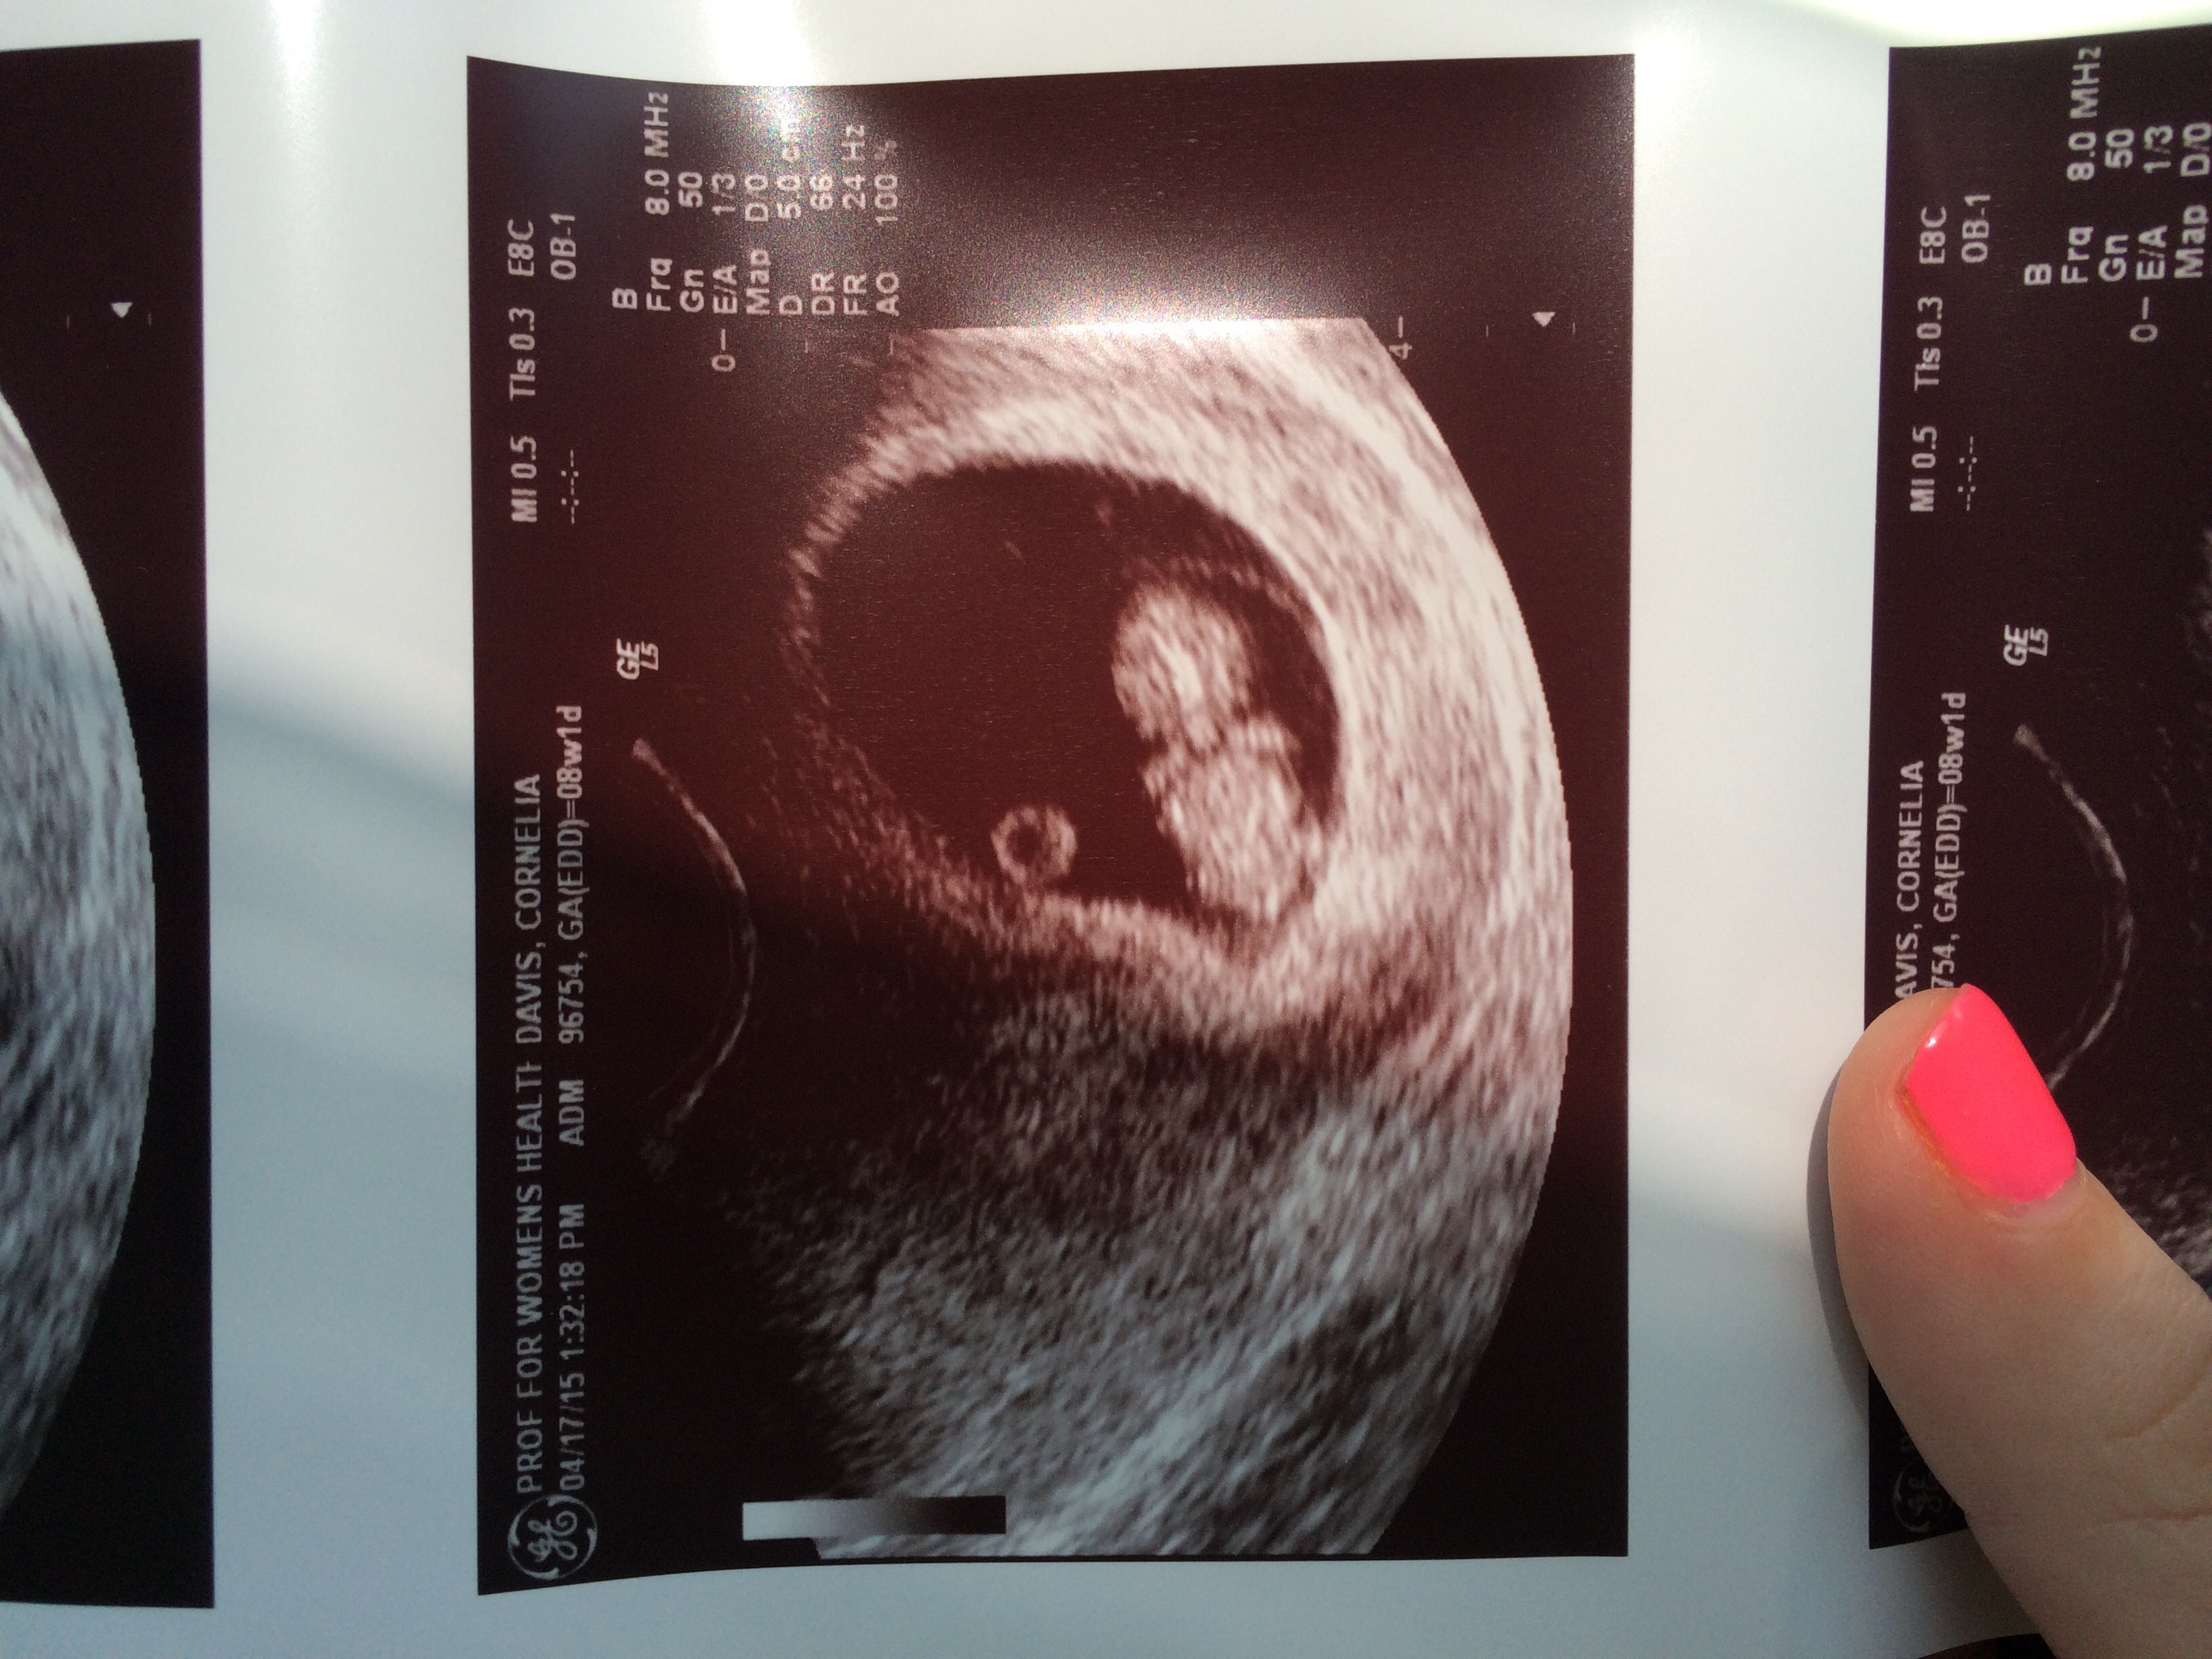

This was when I was 8 weeks! I think I'm a little farther than what they think though. I go Friday for my 12week check up (even though that's my first day of week 13